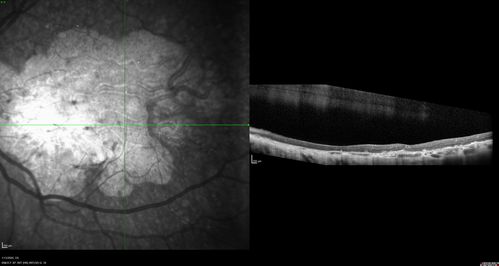

Severe Geographic Atrophy from Dry Age-Related Macular Degeneration

90 year old female with severe vision loss over the last few years.

VA 3/200 OD

1/200 OS

Geographic Atrophy from Age-related macular degeneration - Large areas